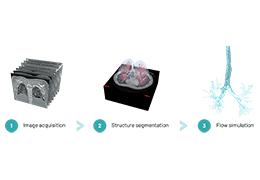

ANYTHINK 经导管主动脉瓣膜置换术分析系统